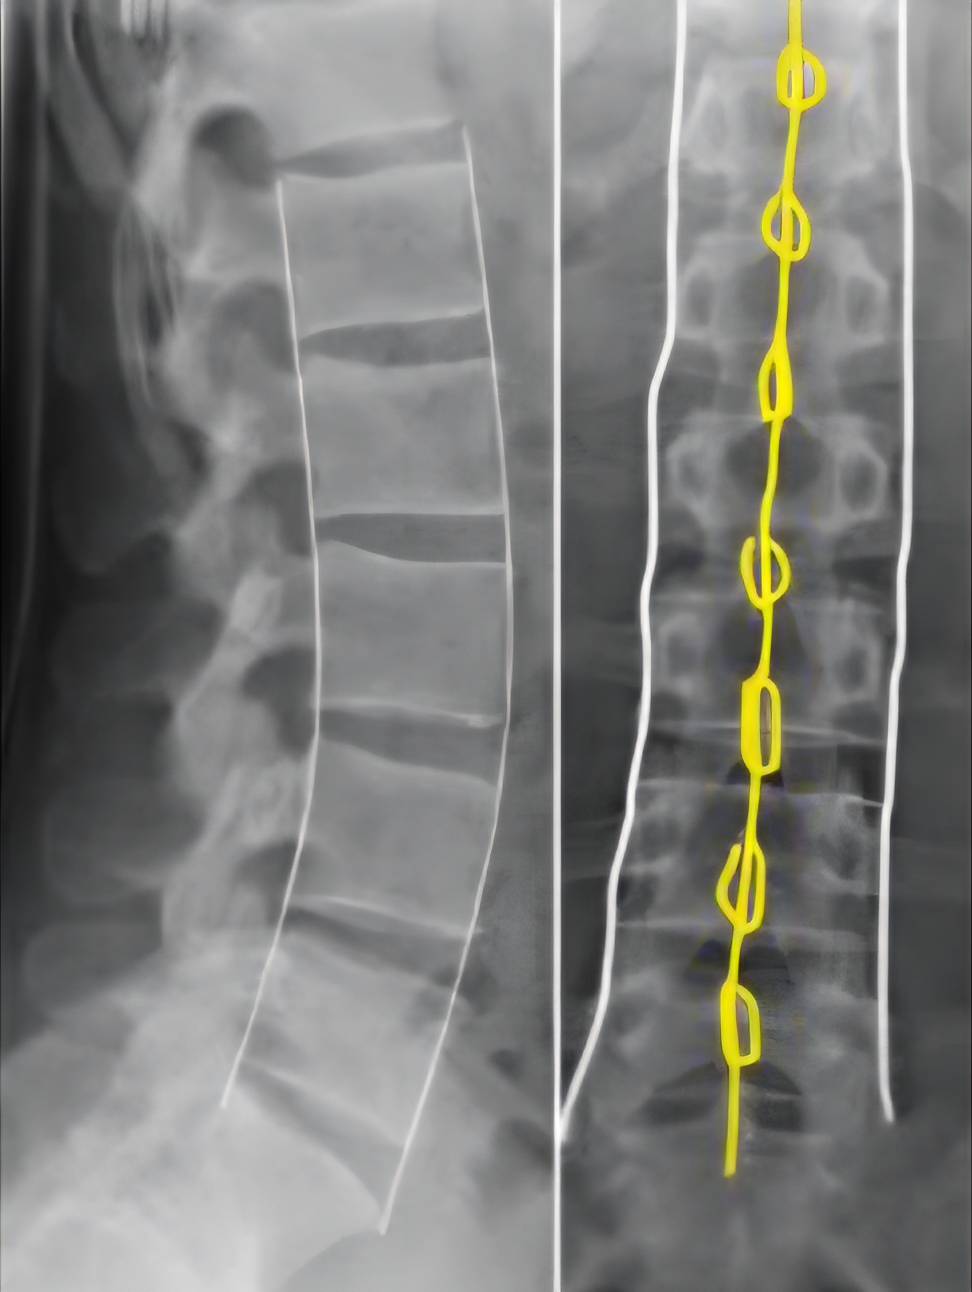

Røntgen

Front- og sidebilder av thorakal og/eller lumbal columna. Husk at smerten ofte projiseres mer distalt enn selve bruddnivået.

På røntgen vurderes:

- Virvelhøyde

- Asymmetri i aksene

- Avstand mellom spinosi i sideplan

- Avstand mellom fremrekanter av corpus

Bildet hentet fra: Tessa Davis . Thoracolumbar spine x-rays, Don't Forget the Bubbles, 2019. Available at: https://doi.org/10.31440/DFTB.17581

Inndeling:

Det finnes flere ulike klassifikasjonssystemer for frakturer i columna. Tradisjonelt har Denis’ klassifikasjonssystem vært mye brukt. I dag benyttes hovedsakelig AO-klassifikasjonssystemet og TLICS for å beskrive omfanget av bruddet.

AO-klassifikasjonssystemet

Brukes for å beskrive bruddet radiologisk og angi mistenkt alvorlighetsgrad. Systemet bygger på tre parametere:

1. Morfologi: Bruddet inndeles i type A (A1–A4), type B (B1–B3) eller type C.

- Type A-frakturer omfatter kun fremre og midtre søyle.

- Type B-frakturer innebærer affeksjon av enten fremre ligamentøse strukturer eller bakre ligamentsystem. Radiologisk sees dette som distraksjon med økt avstand anteriort eller posteriort.

- Type C-frakturer har et element av translasjon, det vil si horisontal eller rotatorisk feilstilling.

2. Nevrologisk status (N0–N4): Graderes ut fra om det foreligger nevrologiske utfall og alvorlighetsgraden av disse.

3. Tilleggskriterier (M1–M2)

- M1 gir mistanke om skade i bakre strukturer.

- M2 indikerer underliggende pasientfaktorer som kan predisponere for skade i bakre strukturer (for eksempel Bekhterev)

Bilde kreditert til: Sander P.J. Muijs, Wouter Foppen, Frank Smithuis and Robin Smithuis. Department of Orthopedic Surgery and Radiology and Nuclear Medicine, University Medical Center Utrecht, University Medical Center Amsterdam, Alrijne Hospital, Leiden, the Netherlands.

The Radiology Assistant : AO Spine Classification of Thoracolumbar Fractures